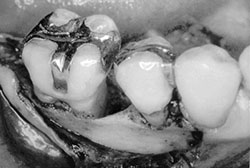

手術清創方法

適用在較大的牙周破壞,清創合併人工骨粉及再生膜,促進骨頭再生